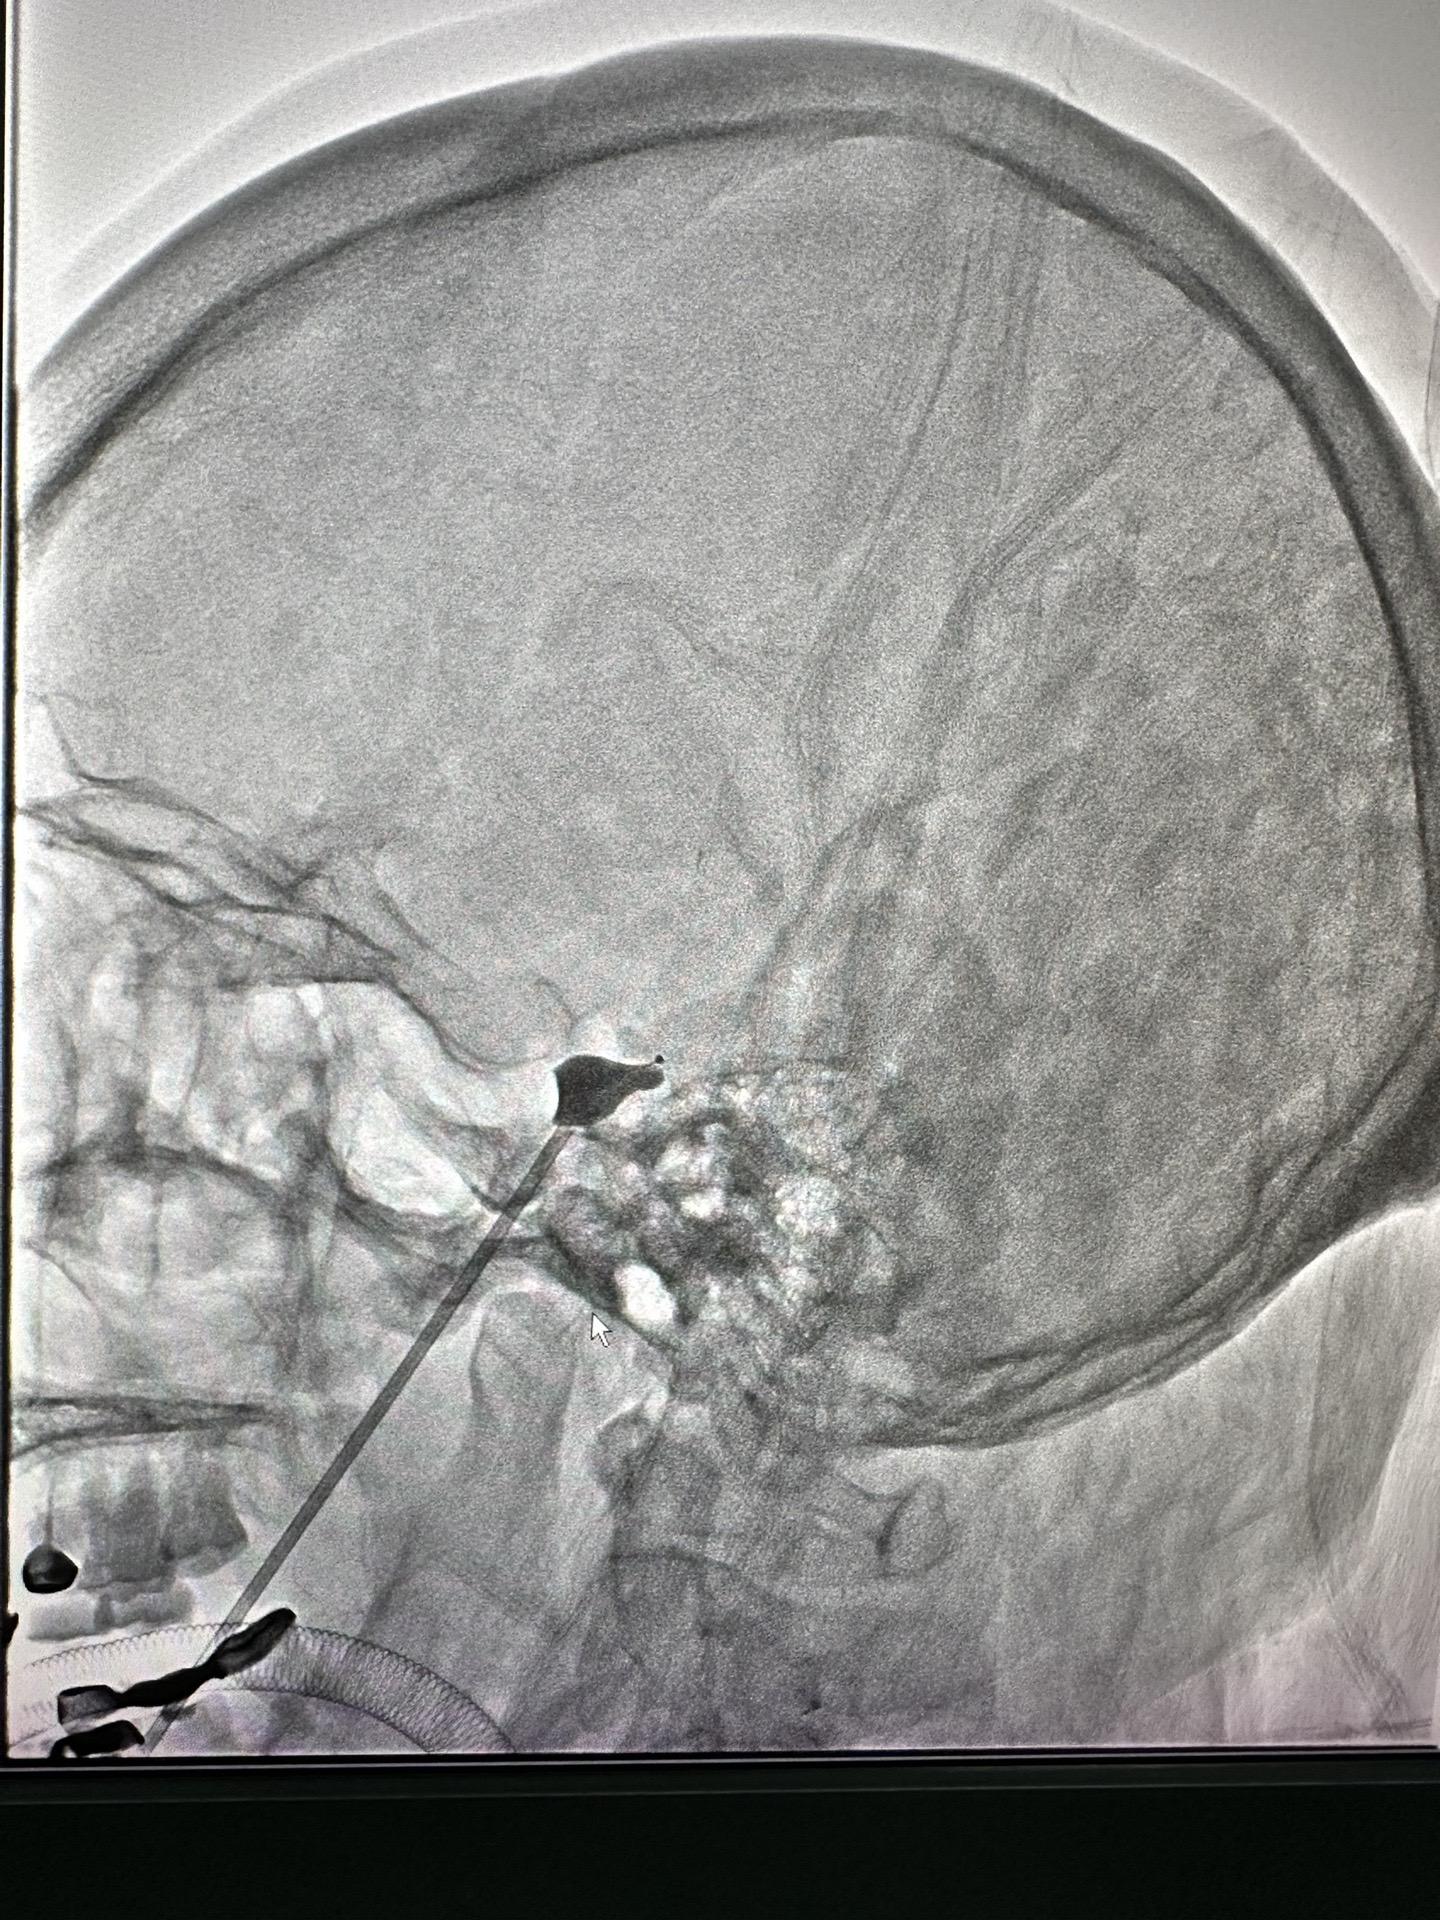

最疼的脸,合并嘴疼的脸。最疼的脸痛,三叉神经痛,利用复合手术室的高科技、高精尖设备用于治疗三叉神经痛有什么好处? 灵活的机械臂、快速的术中Dyna CT、高清的图像,给予患者保驾护航!

最疼的脸,合并嘴疼的脸。最疼的脸痛,三叉神经痛,利用复合手术室的高科技、高精尖设备用于治疗三叉神经痛有什么好处? 灵活的机械臂、快速的术中Dyna CT、高清的图像,给予患者保驾护航!手术室日常